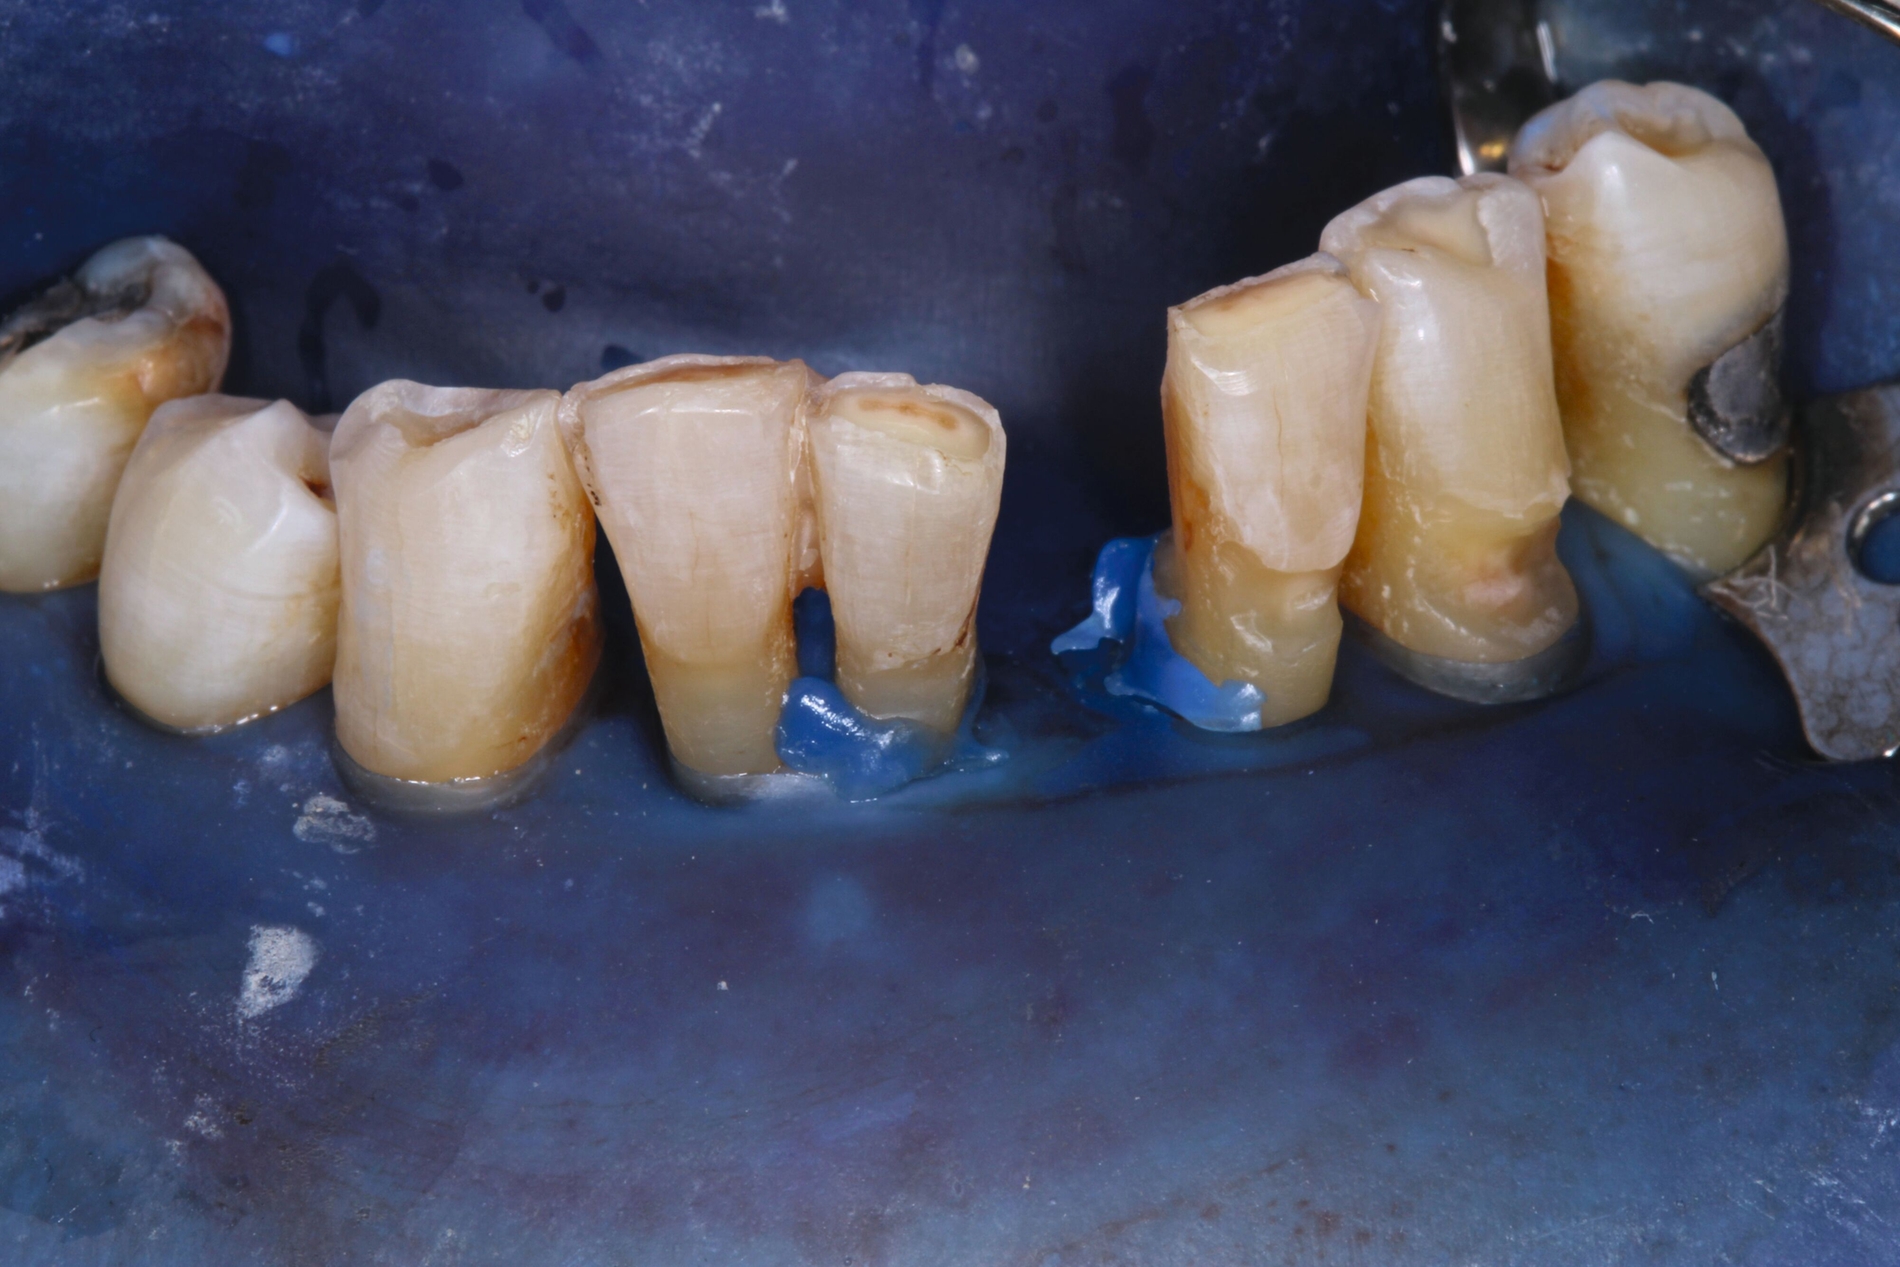

Patientinnen und Patienten mit stark reduzierter Therapiefähigkeit profitieren in besonderem Maß von zeiteffektiven Methoden und Materialien, zum Beispiel Bulk-fill-Kompositen, Reparaturfüllungen, Glasionomerzementen oder Intraoralscans. Die Therapiefähigkeit kann – ähnlich wie in der Kinderzahnmedizin – durch ein vertrauensvolles Verhältnis optimiert werden. Anders als in der Kinderzahnmedizin gibt es in der Alterszahnmedizin aber keine altersassoziierten Kontraindikationen für zahnmedizinische Interventionen. Voraussagbare Therapieergebnisse sind von besonderer Bedeutung, um erneute Behandlungen zu vermeiden. Das gesamte Spektrum zahnmedizinischer Interventionen kann bei der Behandlung von Personen mit Pflegebedarf sinnvoll sein. Die Abbildungen 6 bis 9 zeigen zahnmedizinische Interventionen bei Personen mit ausgeprägter Frailty (Stufe 7 der klinischen Frailty-Skala).